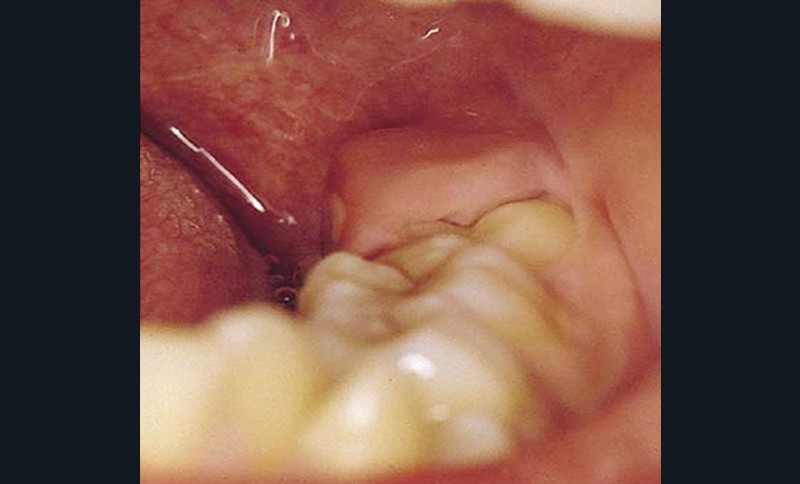

Accidents infectieux : péricoronarite

La péricoronarite est une infection du sac péricoronaire de la dent de sagesse qui peut évoluer vers la formation d’un abcès. Trois formes peuvent être observées : la péricoronarite congestive, la péricoronarite suppurée (fig. 4) et la forme chronique.